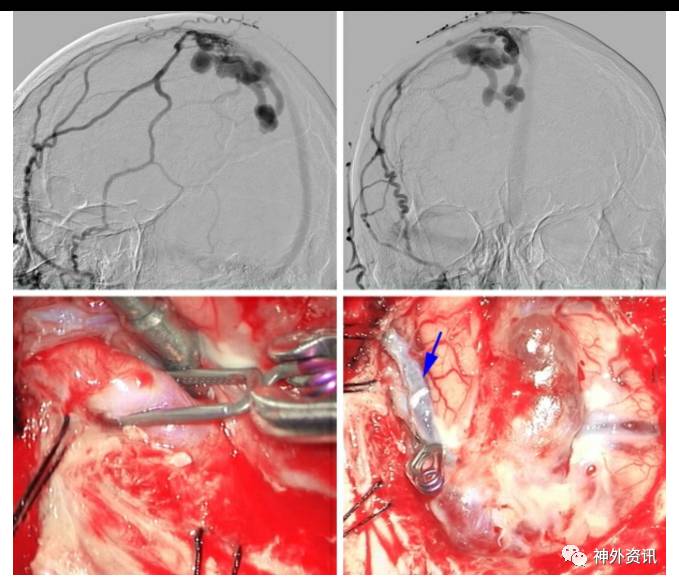

图3. 图示为左侧额骨后方开颅,夹闭向上矢状窦中部引流的单根窦旁dAVF。动脉化的皮层静脉上可见静脉扩张,这种现象在该类型的dAVFs中非常常见,具有较高的出血风险(左图)。在动脉化静脉与静脉窦连接处放置血管夹,导致瘘口闭塞(左图,插图),可见曲张静脉转为暗蓝色(右图)。术中荧光造影确认在扩张或曲张静脉内已呈乏血流状态。无需切除曲张静脉。

图4. 一例自发性右侧矢状窦旁dAVF,主要由硬脑膜中动脉分支供血(上图,侧位和前后位颈外动脉造影)。夹闭汇入上矢状窦的主要动脉化引流静脉(左下图)。接着,相关的皮层曲张静脉和引流静脉都转为蓝色(右下图,箭头)。